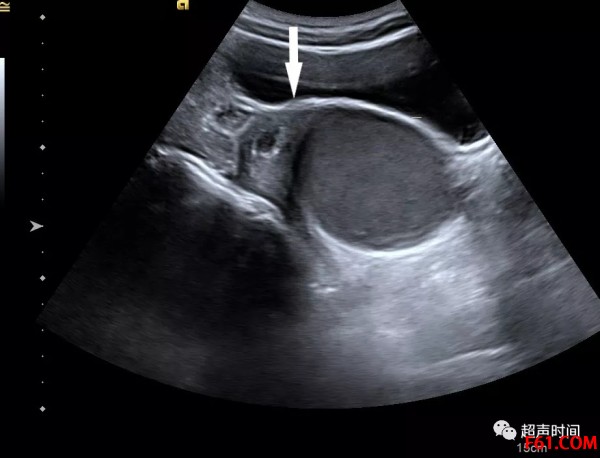

处女膜闭锁超声诊断图

图 2 箭头示囊性回声区与宫腔积液相连

处女膜闭锁的超声典型表现为阴道、宫腔和(或)输卵管、腹腔内探及液性暗区,内可见密集点状回声。

处女膜闭锁时,阴道内的液性暗区下端呈圆柱状,张力高;